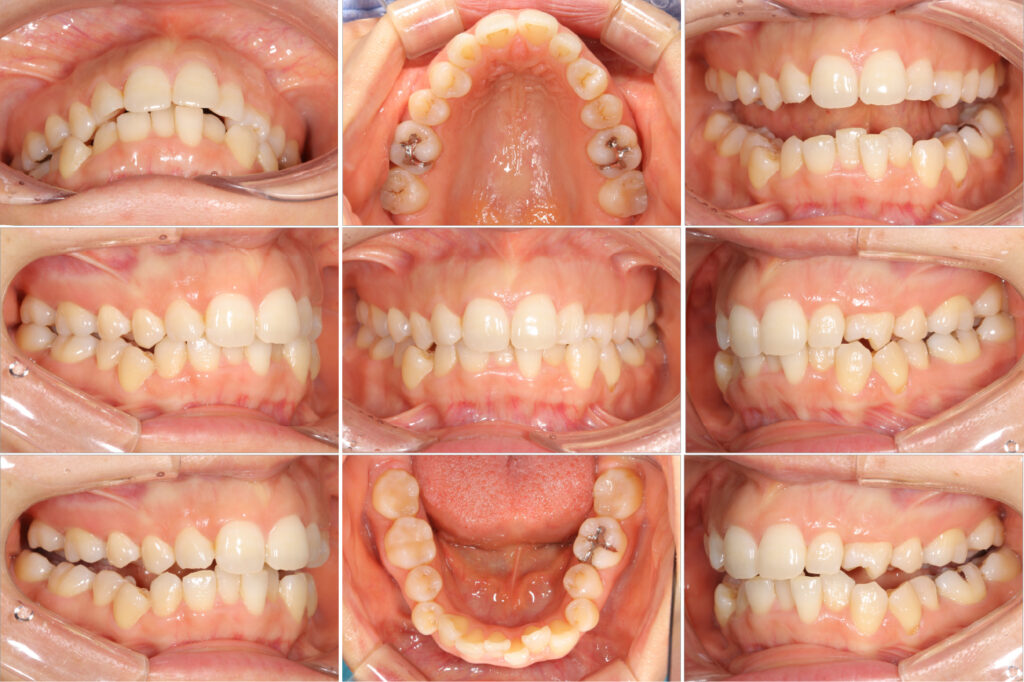

左上4番の捻転が改善しました。

歯並びは綺麗になりました。

矯正治療終了。

奥歯がしっかり咬合しました。

歯並びのガタガタもなくなり綺麗に並びました。

奥歯の咬合状態も良好です。

歯並びのガタガタ(叢生)が気になるとのことで来院されました。

元々、上顎左右の3番目の歯が先天欠如しており、上下で歯の数が異なりました。

上下の歯列のバランスを合わせるためと、下顎のガタガタ(叢生)を綺麗に並べるために、下顎の歯と歯の間を削合しスペースを作って綺麗に並べました。

左上の捻転している歯は、アタッチメントを2箇所に設置することで回転させて治しました。

矯正の後半では、マウスピースにカットを入れてVの字でゴムをかけることで歯を挺出させて、奥歯をしっかり咬合させました。